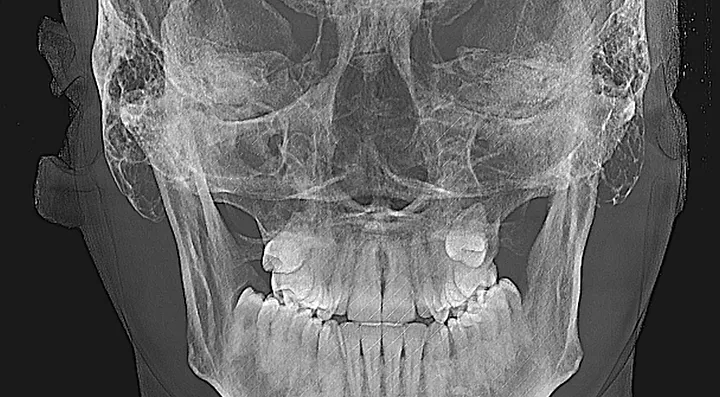

look how the maxilla was ripped apart on this one holy chit

87f545_bc43680091984bbdb74de17eb337bbfd~mv2_d_1920_1280_s_2.webp

87f545_f42d29ecf80a4b9fa8b3f13471579528~mv2_d_1920_1280_s_2.webp

87f545_1c85956a5c2243d1acfc7176f18e69a7~mv2_d_1920_1280_s_2.webp

87f545_91b464f1d91749a39ae126d3341b6d30~mv2.webp